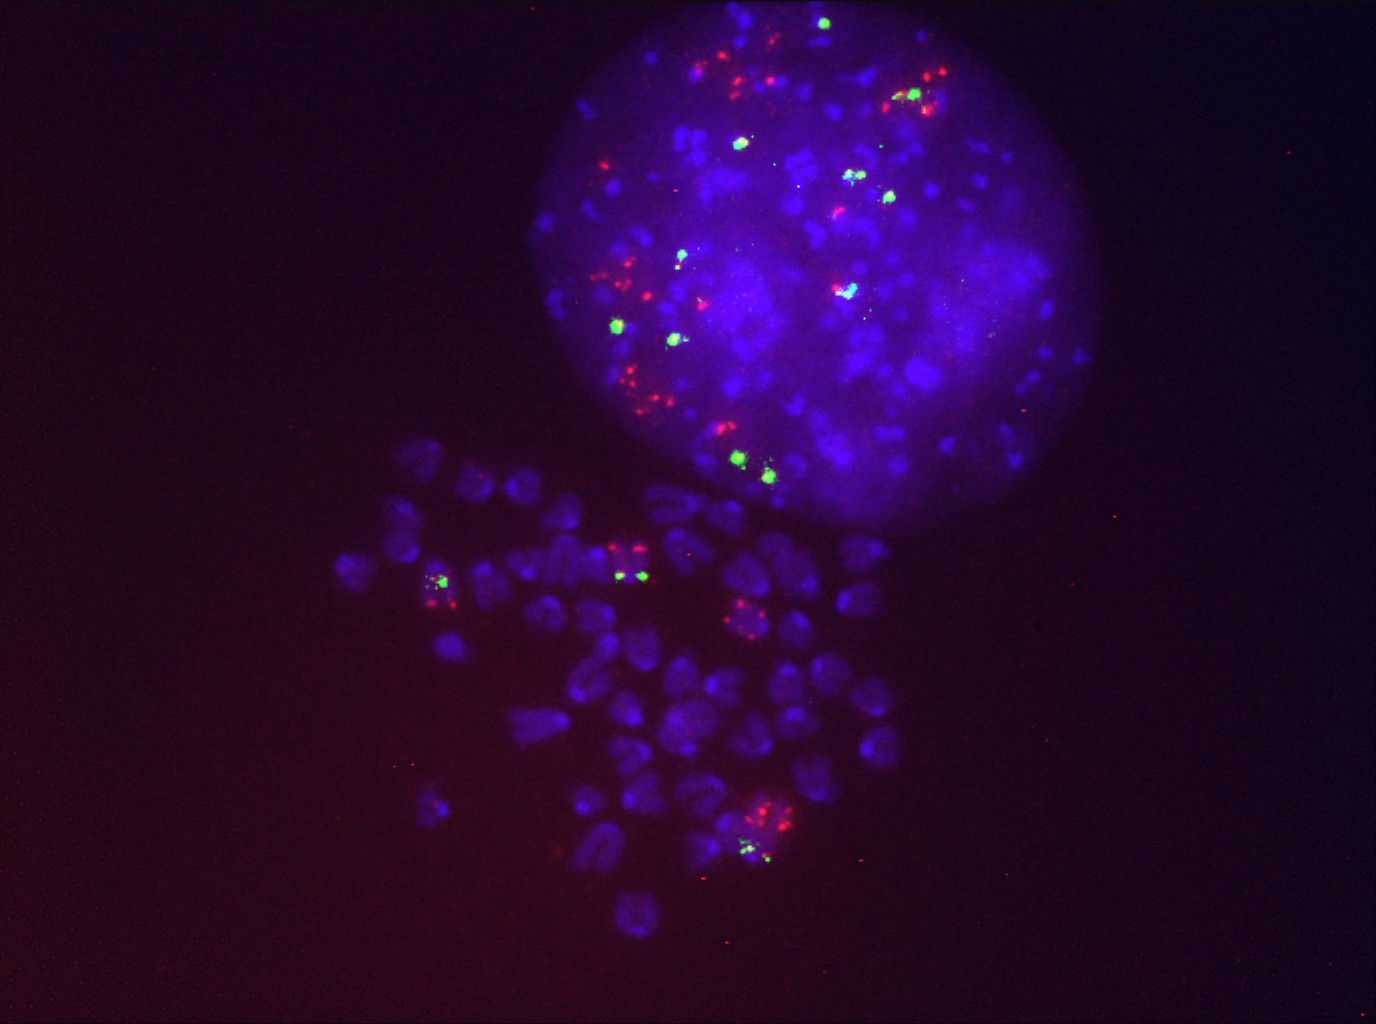

Uno de los grandes avances de las últimas décadas en la investigación del cáncer ha sido el desarrollo de terapias personalizadas, que se dirigen a la biología específica de cada tipo de tumor. Su éxito se debe a que actúan sobre genes y proteínas específicas implicadas en el crecimiento y la supervivencia de las células cancerígenas. Teniendo en cuenta que una cuarta parte de los cánceres de pulmón tienen mutado el gen KRAS, las terapias personalizadas frente a este gen supondrían un gran avance en el tratamiento de los pacientes con cáncer de pulmón. De hecho, en 2021 fue aprobado en Estados Unidos el primer fármaco personalizado (Sotorasib), dirigido a la mutación de KRAS más frecuente en el cáncer de pulmón, que es consecuencia directa del tabaquismo. Específicamente, Sotorasib inhibe la isoforma mutante KRASG12C. Sin embargo, existe un problema, la mayoría de los pacientes de cáncer de pulmón desarrollan rápidamente resistencia al fármaco y el tratamiento deja de ser efectivo.

El grupo dirigido por Drosten estudia cómo surge la resistencia a Sotorasib para prevenirla desarrollando estrategias mejoradas. Para ello utiliza modelos de ratón modificados genéticamente, con mutaciones activadoras en KRAS y otros genes mutados, y desarrolla tumores agresivos similares a los humanos. “Hemos visto que una de las mejores estrategias para tratar estos tumores es inhibir a KRAS. Hemos constatado la regresión del tumor y la curación en todos los casos cuando se elimina por completo el gen KRAS mutado”, destaca el científico del CSIC.

Por otra parte, se ha demostrado que la resistencia se produce porque los tumores pueden adaptarse rápidamente a la presencia del inhibidor. Y como respuesta al tratamiento, las células tumorales de pulmón aumentan las copias del gen KRAS. Además, se ha detectado en este estudio una segunda causa que explica la resistencia al fármaco y la disminución de su actividad: se activan programas transcripcionales (que permiten la conversión del ADN en ARN) que aumentan la modificación química de los fármacos. “Estos mecanismos estudiados en el ratón también están presentes en algunos tumores humanos. Por tanto, los resultados de esta investigación pueden ayudar a identificar nuevas formas de tratamiento adaptadas para cada paciente”, señala Marina Salmón, primera autora del trabajo e investigadora del CNIO.